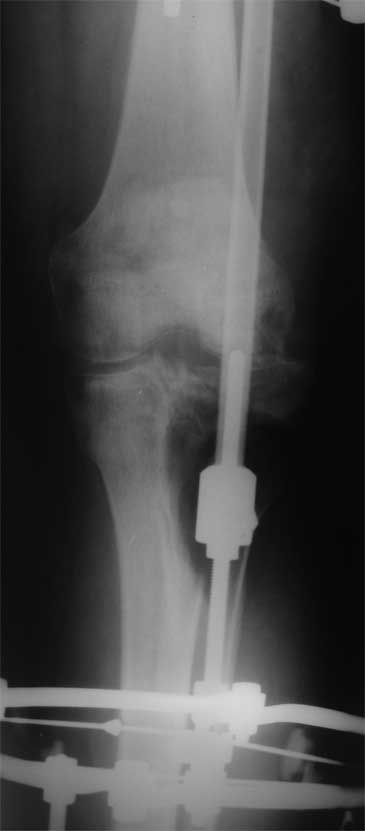

Поступил пациент 40 лет

Производственная травма. Лечился в гнойной хирургии - обширные раны голени.7 мес

пребывания в аппарате (на фото), по УЗИ - тромбоз глубоких вен с признаками реканализации.

Какую тактику лечения предпочесть? Планирую замещение костного дефекта цементом с а/б,

укрыть латеральной головкой икроножной мышцы, на нее кожную пластику. Опыта подобных

операций нет, переправить пациентка в другое более сведущее ЛПУ не получается (ко всему

прочему пациент абсолютно без денег, производство исчезло) Предпочесть другие варианты,

какие? Помогите с материалами по теме, книги, презентации, видео) Master technic b color

atlas у меня есть) Заранее благодарен.